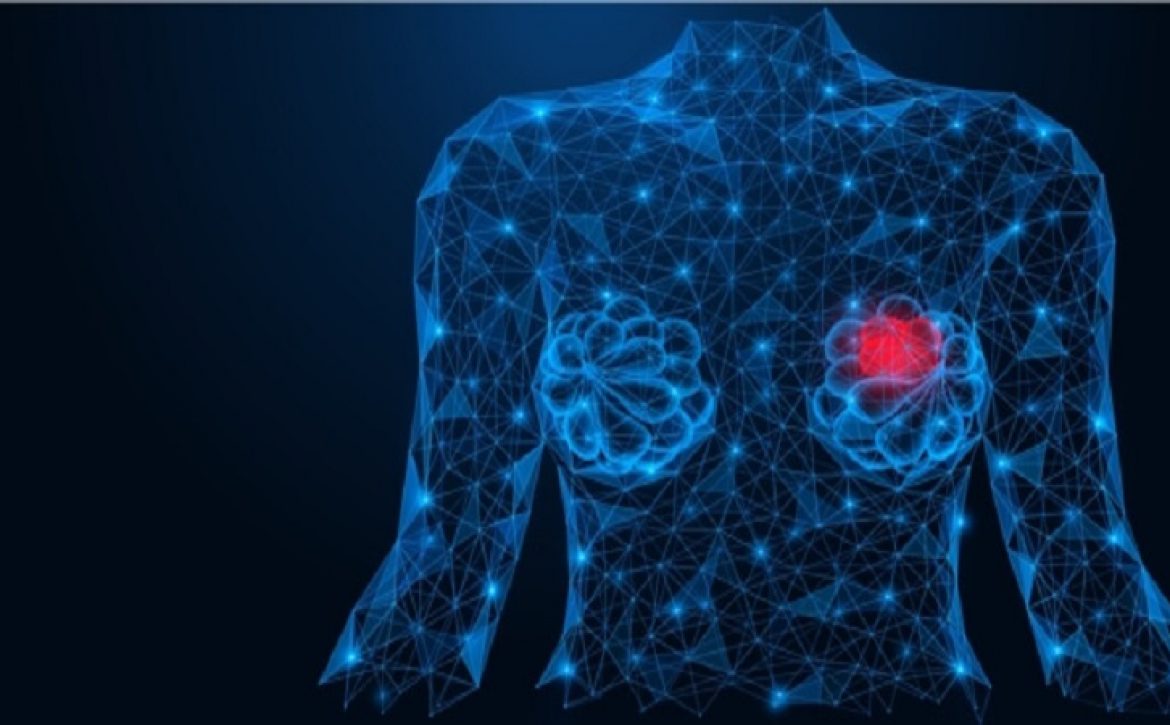

في معظم الحالات ، يكون ألم الثدي من أعراض أمراض الثدي الحميدة وغير السرطانية ونادرًا ما يشير إلى سرطان الثدي. يجب التحقيق في ألم الثدي غير المبرر الذي لا يزول بعد دورة شهرية أو دورتين ، أو يستمر بعد انقطاع الطمث ، أو ألم الثدي الذي يمكن أن يكون مرتبطًا بالتغيرات الهرمونية.

يمكن أن تؤدي التغييرات في مستوى الهرمونات إلى تغيرات في قنوات الحليب والغدد الثديية. يمكن أن تسبب هذه التغييرات تكيسات مؤلمة بالثدي. يمكن أن يحدث ألم الثدي غير الدوري بسبب الصدمة أو تاريخ جراحة الثدي أو حالات أخرى.

في بعض الحالات ، لا يمكن التشخيص النهائي لحدوث آلام الثدي ، ولكن هناك بعض العوامل التي تزيد من احتمالية حدوث هذا الألم. مشتمل: